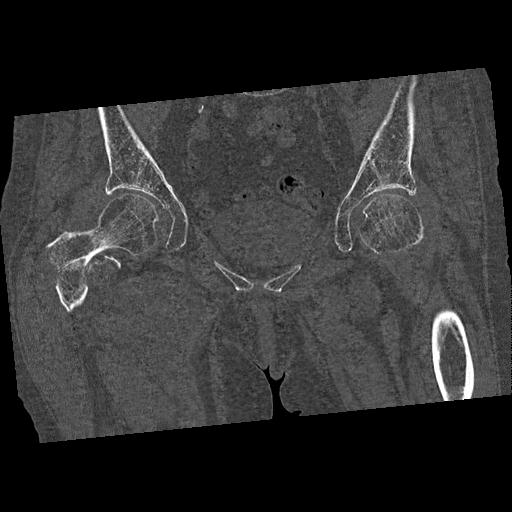

46666 1/28 両股正面+軸と 1/26 右手関節 2R 76歳女性 右転子部骨折